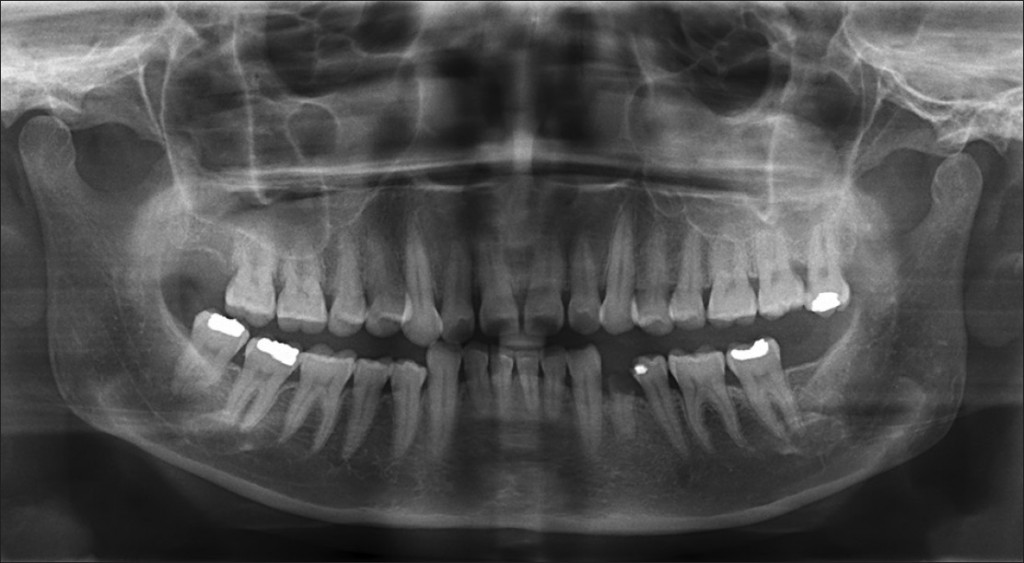

Perhaps you’ve been to the dentist recently, and you put your hands on some bars while the hygienist took an x-ray and the machine spun a portion around you to take the x-ray. Chances are that the x-ray that they took was called an Orthopantomogram, or OPG x-ray, and it was used to give the dentist a panoramic view of all your teeth on just a single film. This technique is becoming more common and is one of the best ways to get an x-ray of your mouth. Through using OPG technology, your dentist can get a better view of your mouth, with more detail about your dental health, while often reducing the amount of radiation that you’re exposed to. Here are four important things that you should understand about OPG.

- It will give you a better idea of your dental health than other methods. Studies have found that the ability to diagnose cavities and other dental health problems was much more efficient using panoramic x-ray technology. You probably spend a lot of time caring for your mouth and making sure that everything is okay. It’s important that the same kind of attention and care is also used in the diagnosis of your dental health. Ask your dentist whether they use OPG in the rendering of dental images, because it will give them a more defined, more clear view of your mouth that will help them make more informed decisions about how to help you.